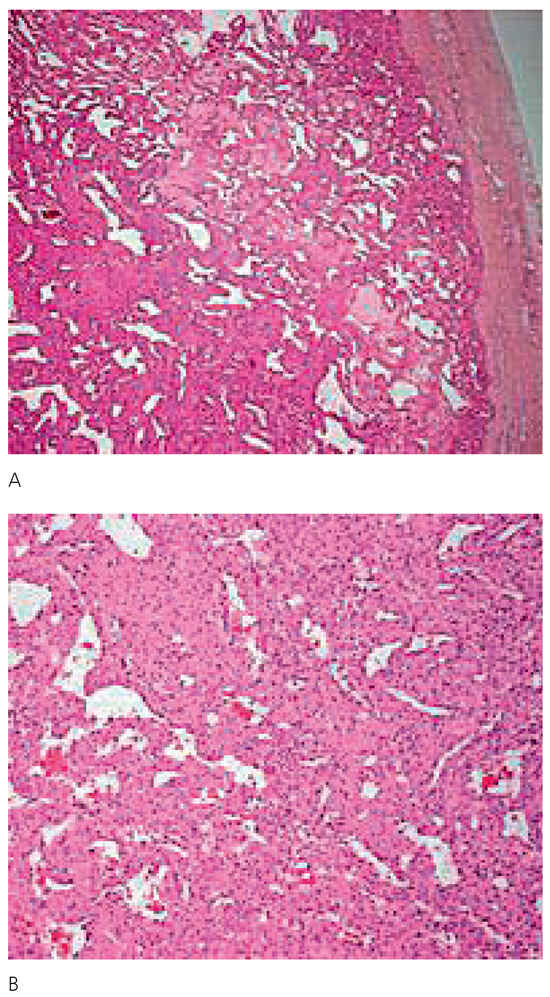

Clinical status showed: BP 150/65 mm Hg. Pulse regular at 82 beats per minute. Peripheral oedema was absent. Several peripheralsigns of aortic regurgitation were noted and a 3/6 protodiastolic murmur was present. Aortic valve replacement was decided and pre-intervention investigations were planed. Transthoracic echocardiography confirmed the aortic regurgitation grade III with mild dilatation of the left ventricle. Thoracic CT scan showed a 30 mm mass located within the left posterior wall (Figure 1). Transoesophageal echocardiography confirmed the location and dimensions of the tumour (Figure 2) and showed in addition involvement of the left atrial wall. Resection of the mass was performed during valve replacement (Figure 3). A 3 cm friable mass attached to the posterior wall of the atrium was easily removed. Reparation of the atrium was performed and a 23 mm aortic artificial valve was implanted. The outcome was uneventful. Histological and immunohistochemical examination conclude to a benign tumorous process compatible with the diagnosis of glomangiopericytoma (myopericytoma) (Figure 4). This was an unexpected diagnosis since to our knowledge it is the first case of cardiac benign haemangiopericytoma reported and secondly because of the patient’s history. A post irradiation tumour would have been more probable. Haemangiopericytoma is a rare tumour. The few one located in the heart were malignant.

Figure 4.

Histology of the tumor. A Vacuolar tissue typical for vascular tumor is seen. B The diagnosis of vascular tumor is confirmed by the architecture of the cells with microvascularisation and absence of signs of malignancy.